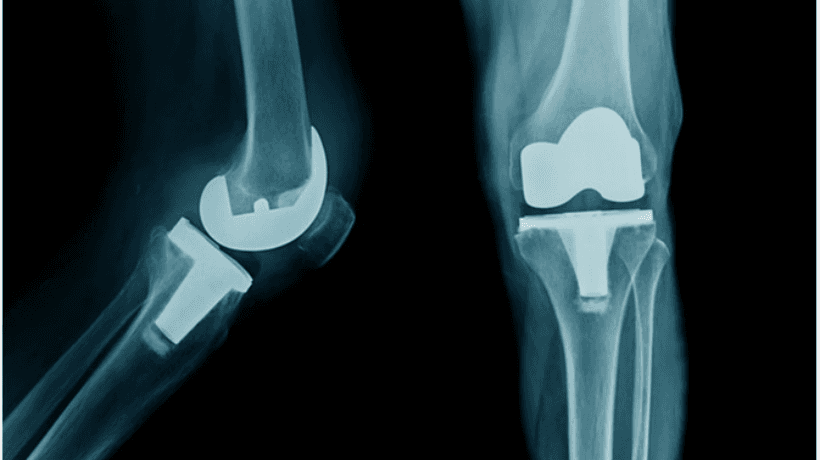

Pembedahan lutut biasanya merujuk kepadapenggantian lutut keseluruhan yang boleh dilakukan dengan cara terbuka yang lama atau dengan teknik moden yang kurang invasif yang dikenali sebagai artroskopi lutut.

Pakar Ortopedik menggunakan implan dan melaksanakan pelbagai teknik moden untuk memberikan bantuan yang diperlukan kepada pesakit. Berikut adalah jenis-jenis pembedahan penggantian lutut dilakukan:

- Jumlah penggantian lutut

- Penggantian lutut separa / Uni petak

- Penggantian tempurung lutut (Patellofemoral Arthroplasty)

- Penggantian lutut yang kompleks atau semakan

- Pembinaan semula ligamen lutut